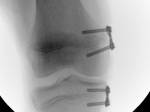

- Figg. 11 A-B-C: intervento di osteotomia

La correzione può essere attuata mediante intervento di osteotomia (fig 11), femorale o tibiale, a seconda della sede della deformità, oppure mediante interventi di modulazione della crescita, epifisiodesi asimmetrica temporanea, mediante applicazione di piccole placche a forma di “8” a cavaliere del versante interno della cartilagine coniugale del femore e/o della tibia (fig 12). Si tratta in questo caso di un intervento più semplice e meno aggressivo, che non richiede alcuna immobilizzazione in apparecchio gessato.

- Fig. 12C: aspetto RX dopo impianto delle placche sul versante mediale della cartilagine coniugale del femore e della tibia.